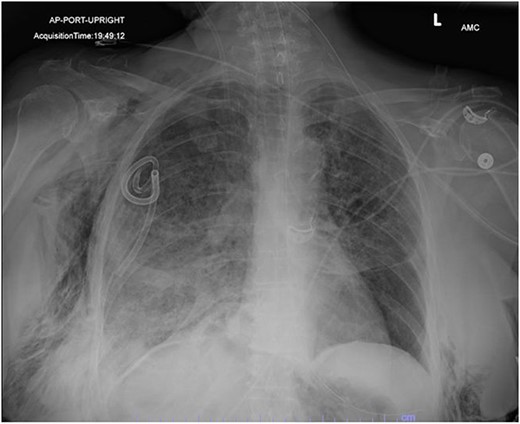

On Hospital Day 2, an interval CXR showed continued resolution of the right-sided pneumothorax but worsening subcutaneous emphysema of the bilateral chest wall and pneumoperitoneum (Fig. 3). Surgical consultation was sought, leading to diagnostic laparoscopy. In the abdomen, emphysematous changes within the gastrohepatic ligament and omental adhesions to the anterior abdominal wall were visualized (Figs 5 and 6). Laparoscopic exploration revealed no diaphragmatic injury or perforated viscera but identified emphysematous changes throughout the preperitoneal space, small and large bowel mesentery, and right paracolic gutter (Figs 7 and 8). Immediate post-op CXR no longer showed evidence of pneumoperitoneum (Fig. 4). The patient was transferred back to the ICU and extubated after three days on Day 5. After the removal of chest tube and transfer to a medical floor on Day 8, the patient developed aspiration pneumonia that was treated with antibiotics. She was discharged on Day 15.

Post-operative chest radiograph showing increased diffuse subcutaneous emphysema in chest, lower neck and upper left abdominal wall. Previously demonstrated pneumoperitoneum is not visualized on the current film.